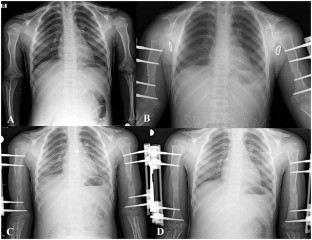

Fig. 3